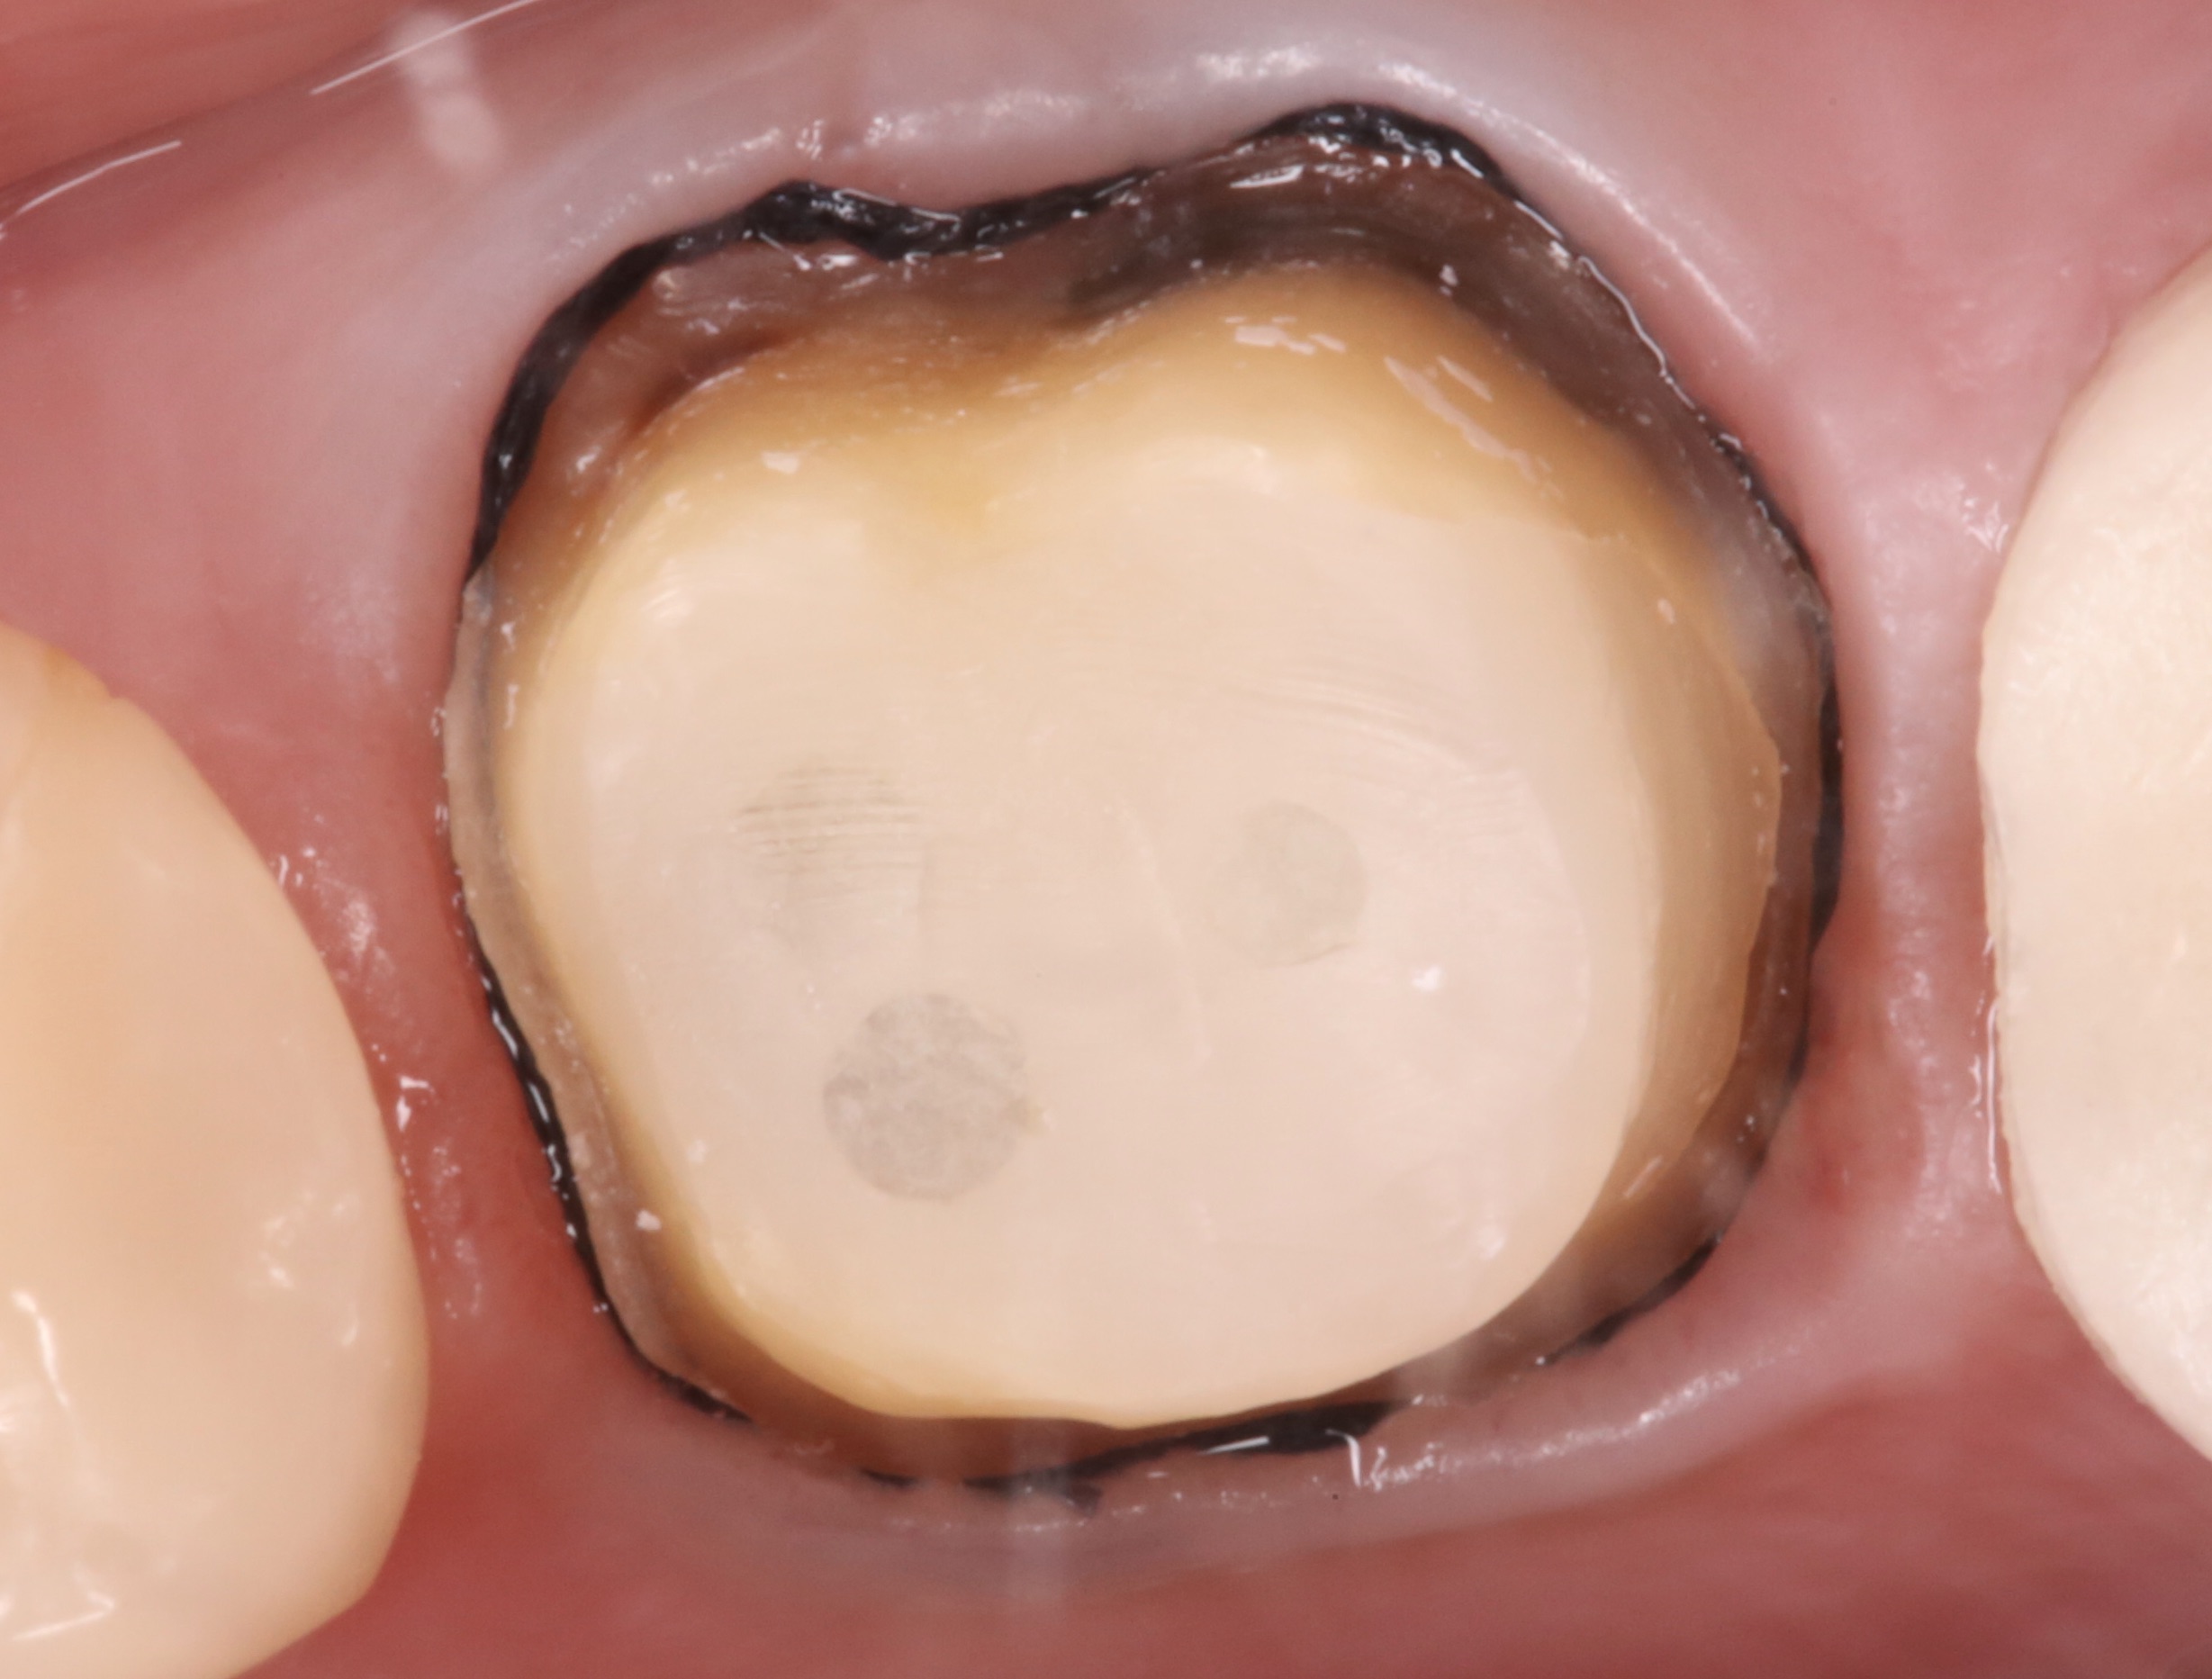

これは型取りする直前の歯の状態です。

歯の周りが黒くなっているのがお分かりいただけると思います。

これは型取りする前の下準備で、歯ぐきを触って刺激してしまう処置です(圧排処置と言います、痛くはありません)。

この際、歯ぐきが炎症を起こしていると充分に完了することができません。

写真のように炎症がなく、全く歯ぐきが腫れていない状態にして型取りに臨むことが求められます。

これを達成するのに必要なのが仮歯です。

仮歯で歯と歯ぐきの周辺の環境を本歯に近づけることによって、歯ぐきは綺麗に治癒していきます。